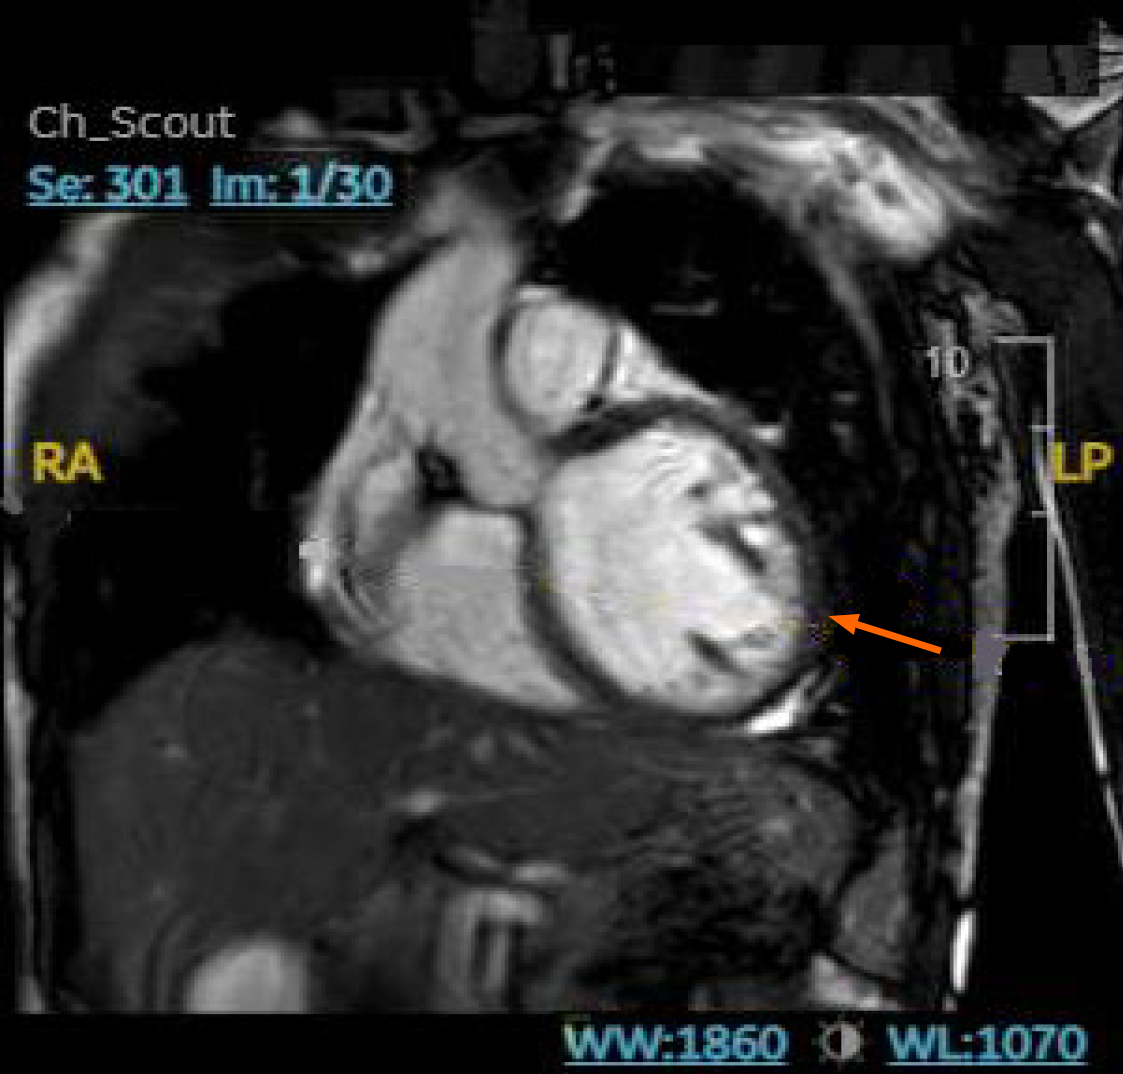

Endoscopic bronchial ultrasound with bronchoalveolar lavage showed increased CD4: CD8 ratio without malignant cells. cMRI was performed and showed LV dilation with severe systolic dysfunction, global hypokinesis, and LGE (Figure 4). Whole body PET revealed patchy perfusion abnormalities in the basal to mid inferior wall and mid septal segments (Figure 5). It also revealed FDG uptake in the lungs without FDG uptake in the heart. Left heart catheterization showed normal coronary arteries, right sided pressures, pulmonary vascular resistance index, pulmonary capillary wedge, left ventricular end diastolic pressure, cardiac output, and valvular function.